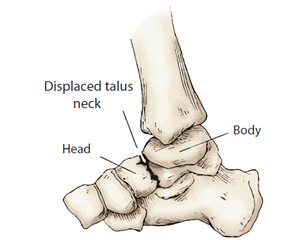

The talus, which has 60–70% of its surface covered in articular cartilage and no muscular attachments, is essential for ankle movement. Talar fractures are uncommon, making up 0.3% of all bone fractures and 3.4% of foot fractures, predominantly affecting males (up to 73%). These fractures typically occur in the neck of the talus and result in significant pain, swelling, and an inability to bear weight, with possible complications including avascular necrosis and post-traumatic arthritis.

Comminuted fractures and fracture dislocations of the talus represent a complex challenge in orthopaedic trauma, often leading to significant morbidity if not managed effectively. The talus plays a crucial role in ankle stability and weight-bearing, making its preservation vital for maintaining function. Among these injuries, fractures of the neck of the talus are particularly concerning, as they frequently result in complications such as osteonecrosis, which can severely impact long-term outcomes.